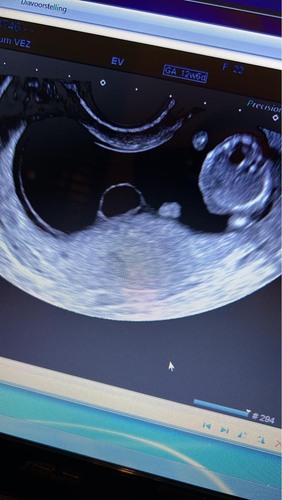

Hier ook met eerste echo een cyste ontdekt naast de baarmoeder.. dit had ik niet bij mn eerste kindje (nu 5 jaar)

vk heeft samen met collega gekeken en beoordeeld dat er nog geen verdere actie nodig was om gynaecoloog mee te laten kijken, de 23e hebben we de termijn echo, toch wel spannend.. al zeggen ze dat het niks is om ongerust over te zijn. Afwachten dus. (was even vergeten dat zwanger zijn soms zenuwslopend wachten is :) vooral het begin, pfff..)